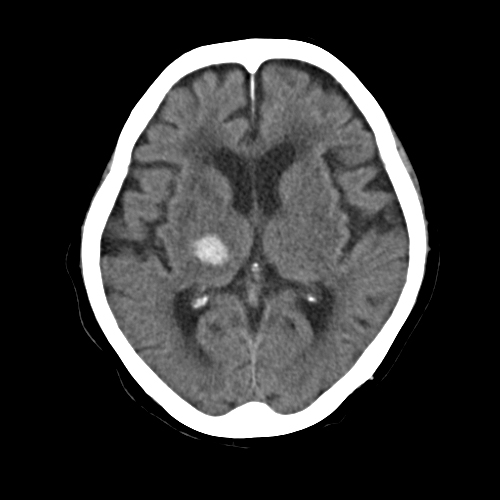

CTによる頭部断層撮影

横断像により脳内出血、脳梗塞、脳腫瘍などの病変を調べます。 左の写真上で白く写っている部分が脳内出血です。